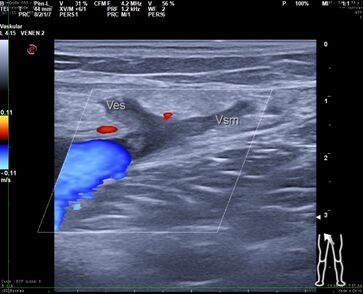

Das Herausreißen der Vene mit dem Stripper ist ein blindes Verfahren, bei dem der Operateur keine Kontrolle darüber hat, wo der Stripper nach Einführen in die Vene entlangläuft. Mehr als 50% der Bevölkerung haben eine Doppelanlage der Vena saphena magna.

Wenn dies nicht durch eine gründliche präoperative Ultraschalluntersuchung durch den Operateur selbst nachgewiesen wurde, wird nur ein Ast gestrippt, durch den verbliebenen zweiten entstehen frühzeitig Rezidivvarizen.

Der akzessorische zweite Saphenaast kann wie die normale Saphena in der gleichen Faszienduplikatur verlaufen, in einer zweiten oder subkutan. Dann wird bei einer Operation durch in der Gefäßanatomie unerfahrene Chirurgen und insuffizienter präoperativer Sonographie der akzessorische subkutane Ast von dem als tiefe Vene fehlgedeuteten intrafaszialen Saphenahauptstamm abgesetzt und gestrippt. Beschwerden und Varizen am Unterschenkel bleiben dann bestehen. Dies ist der häufigste Fehler bei der offenen Krampfaderoperation .